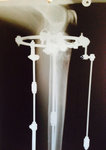

Дата операции 23.01.2015г.

Дата снятия аппаратов 28.04.2015г.

Срок лечения 95 дней.